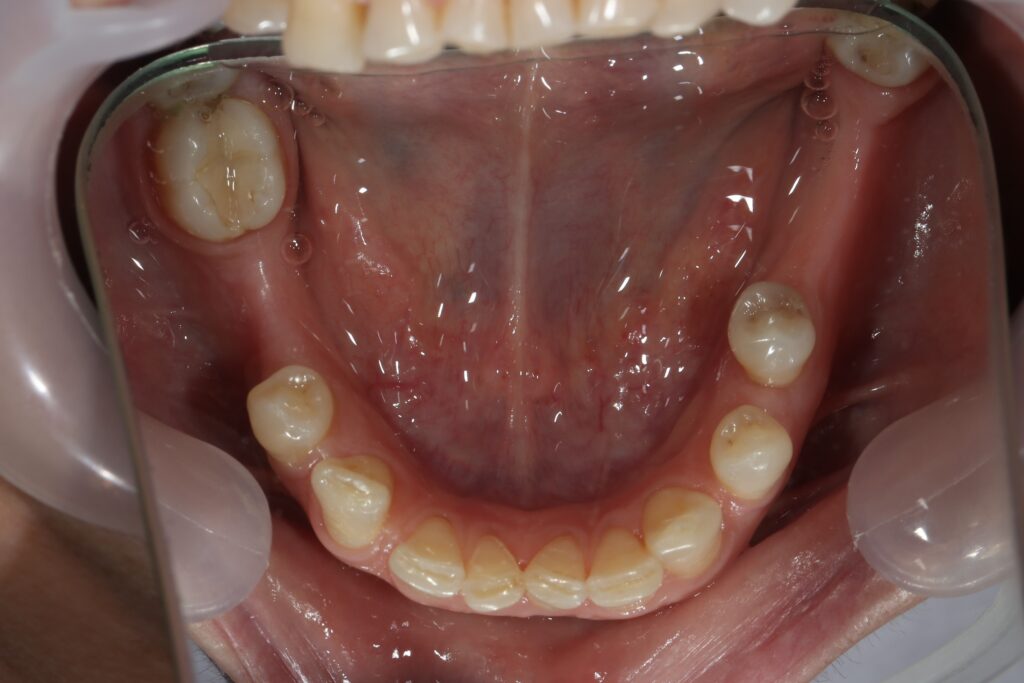

Ситуация до лечения

Из-за множественных давних удалений жевательных зубов, произошла деформация зубных рядов, зубы разъехались в область удаленных, что затрудняло протезирование в момент обращения к ортопеду.

Так же можно отметить сильное снижение высоты прикуса (верхние зубы на 100% перекрывали нижние, что вызывало хроническую травму десны), а также повышенную стираемость твердых тканей зубов, что является следствием повышенной нагрузки, которую много лет испытывали передние зубы, в связи с отсутствием жевательных зубов.